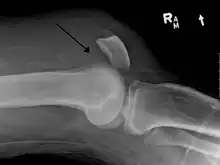

An x-ray demonstrating quadriceps tendon rupture. Note the abnormal angle of the patella and soft-tissue swelling marked by the arrow.